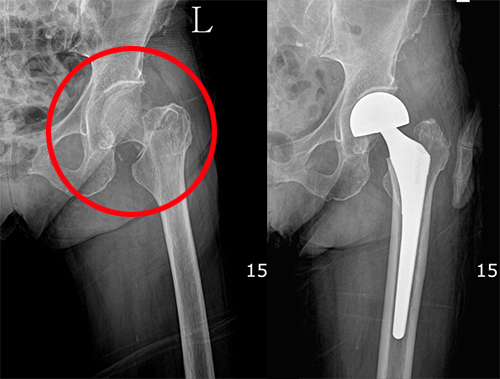

고관절 통증 증상 5.고관절의 무혈성 괴사

무혈관성 괴사란 혈액 순환 장애로 인해 혈액 공급이 원활하지 못하여 뼈가 썩는 병입니다. 대퇴골두 무혈관성 괴사는 허벅지 뼈, 즉 대퇴골의 머리 부분에 피가 통하지 않아 이 부분이 괴사 하게 되는 것입니다. 대부분 30~50대에게 발생하고, 여성보다는 남성에게 더 많이 발생합니다. 약 60% 이상은 양쪽 고관절의 대퇴골두 무혈관성 괴사를 겪습니다. 대퇴골두 무혈관성 괴사를 일으키는 위험 인자로는 음주, 부신피질 호르몬 투여, 고관절 부위 외상, 잠수병, 통풍, 혈청지질 이상, 만성 신질환, 만성 췌장염 등이 있습니다. 이 중에서도 음주와 부신피질 호르몬제가 전체 원인의 90% 정도를 차지합니다.

대퇴 경부 골절은 대퇴 골도로 가는 혈관이 손상되어 대퇴 골도의 무혈성 괴사와 불유합을 초래할 수 있기 때문에 응급으로 내 고정술을 시행하는 수술적인 치료가 필요합니다.